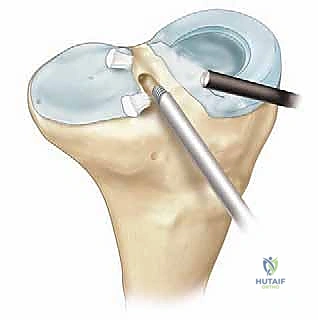

الخطوة الأولى: التنظير التشخيصي وتحضير المفصل

يبدأ الدكتور هطيف بإجراء شقوق صغيرة جداً (Portals) لإدخال كاميرا المنظار (بتقنية 4K عالية الوضوح). يتم استكشاف المفصل بالكامل. يتم تنظيف أي بقايا من الغضروف الهلالي القديم التالف، وتحضير حافة الكبسولة (Bleeding bed) لتشجيع التروية الدموية والالتئام مع الطعم الجديد.

الخطوة الرابعة: إدخال الطعم وتثبيته

من خلال شق جراحي صغير (Mini-arthrotomy)، يتم سحب الطعم بلطف إلى داخل الركبة باستخدام الخيوط التي تم تمريرها عبر الأنفاق العظمية. يتم التأكد من استقرار السدادات العظمية داخل الأنفاق.

الخطوة الخامسة: الخياطة المحيطية الدقيقة (Peripheral Suturing)

هذه هي الخطوة الأكثر حيوية. يجب خياطة محيط الغضروف الهلالي الجديد بكبسولة الركبة للمريض بشكل محكم ومتقارب جداً. يستخدم الدكتور هطيف تقنيات خياطة متعددة بالمنظار:

* تقنية من الداخل للخارج (Inside-out): تعتبر المعيار الذهبي للغضروف الهلالي، حيث يتم تمرير إبر طويلة من داخل المفصل إلى خارجه لتثبيت الغضروف بالكبسولة.

* تقنية من الخارج للداخل (Outside-in): تستخدم لتثبيت الجزء الأمامي من الغضروف.

* تقنية الخياطة الداخلية بالكامل (All-inside): تستخدم أجهزة تثبيت حديثة لبعض الأجزاء الخلفية.